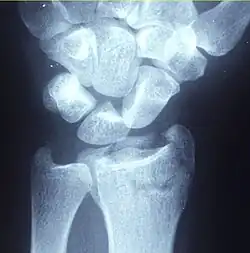

X-ray of a displaced intra-articular distal radius fracture in an external fixator: The articular surface is widely displaced and irregular.

Diagnosis may be evident clinically when the distal radius is deformed, but should be confirmed by X-ray. The differential diagnosis includes scaphoid fractures and wrist dislocations, which can also co-exist with a distal radius fracture. Occasionally, fractures may not be seen on X-rays immediately after the injury. Delayed X-rays, X-ray computed tomography (CT scan), or Magnetic resonance imaging (MRI) can confirm the diagnosis.

Fracture with a dorsal tilt: Dorsal is left, and volar is right in the image.